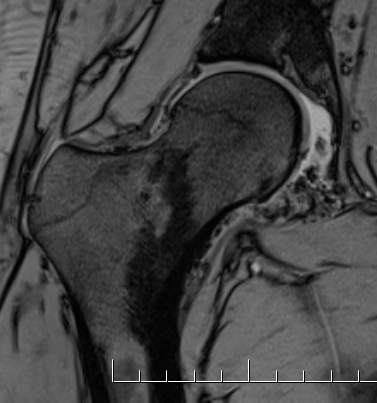

MRI

Synovial thickening

Hemosiderin

- low signal intensity on TI and T2 - "drop out" signals

- blooming on gradient echo

Severe diffuse PVNS with bony involvement